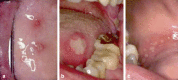

Background: Chronic recurrent oral aphthous ulcers are the most common type of inflammatory efflorescence of the oral mucosa, with a prevalence of 2% to 10% in Caucasian populations. To treat them properly, physicians should know their clinical appearance and course, conditioning factors, underlying causes, and differential diagnosis.